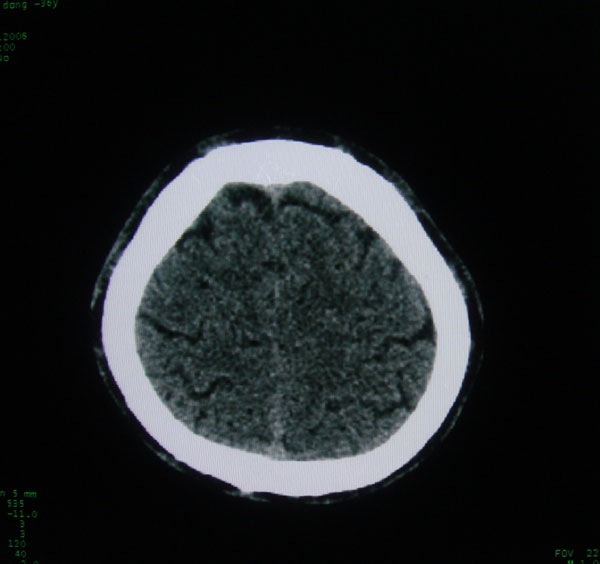

以下是引用拾荒者在2008-6-7 13:05:00的发言:[br]左侧顶骨局限性骨质缺损,边缘锐利,无硬化边,周围软组织轻度肿胀,无明显软组织肿块及骨膜反应,考虑嗜酸性肉芽肿可能。